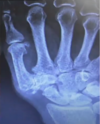

Osteoartrite

Joanete

Hálux valgo